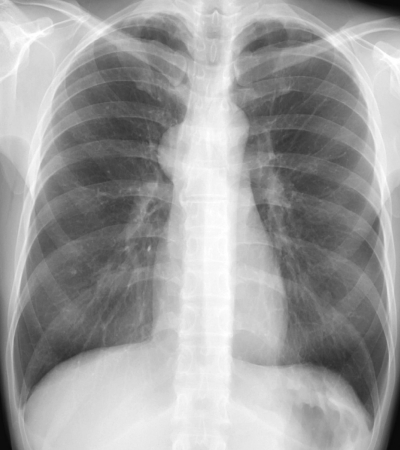

28歳の女性。健診で胸部の異常陰影を指摘されたため来院した。胸部エックス線写真と胸部CTとを示す。

診断のために必要性が低い検査項目はどれか。

a. hCG

b. β-Dグルカン

c. 可溶性 IL-2受容体

d. α-フェトプロテイン(AFP)

e. 抗アセチルコリン受容体抗体